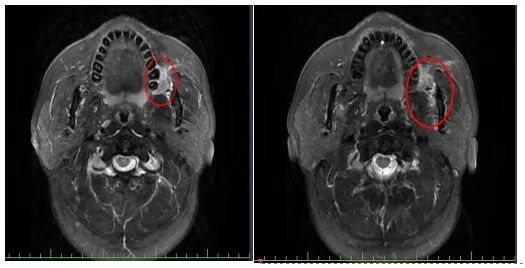

此时朱大哥脸颊内侧的这个“溃疡”已经长到了圣女果那么大,表面弹坑样,摸上去很硬,核磁共振结果也显示他左侧颊部有个肿物,紧贴左侧的上颌骨。尽管朱大哥始终难以相信,没有太大不适症状的他,怎么就可能被肿瘤缠上了,然而,进一步的病理检测结果残酷地显示:左颊高分化鳞状细胞癌。

医院供图